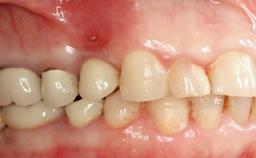

Biological complications caused by undetected cement residue have been receiving much attention. Excess cement might be responsible not only for rapidly developing of peri-implantitis, but also for delayed or chronic manifestations of the disease many years after cementation (Wilson 2009; Linkevicius and coworkers 2013). Invitro and clinical studies have shown that it is very difficult or even impossible to completely clean up excess cement at subgingival margins, so popular in cemented restorations (Agar and coworkers 1997; Linkevicius and coworkers 2011, 2012). Possible outcomes of biological complications due to excess cement range from temporary inflammation of the peri-implant soft tissues without any serious esthetic and functional consequences all the way to implant loss. This report describes a case of peri-implantitis caused by residual cement; as well as the management and quite unusual resolution of the complication. The patient presented in 2009 with a draining sinus tract, tenderness on chewing, and tissue contact above the implant-supported restoration. The implant had been restored approximately three years before.